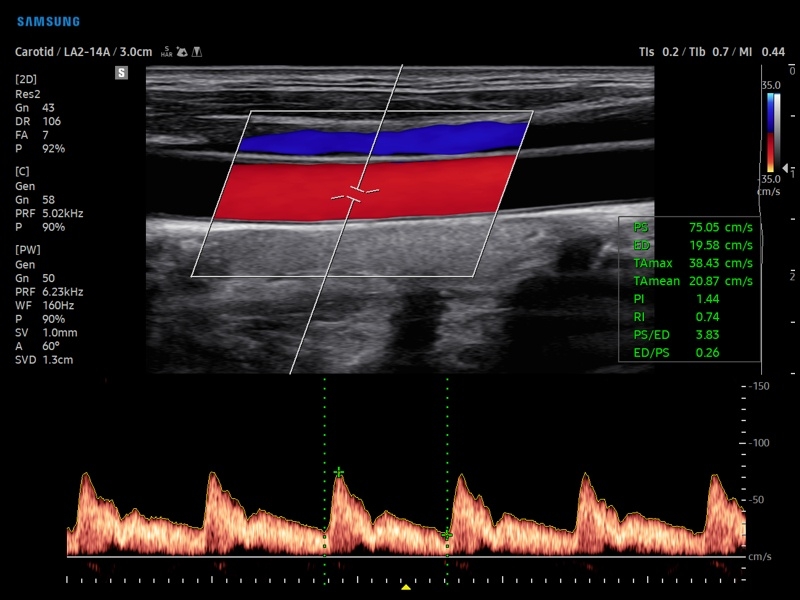

• PW - импульсно-волновой допплер, steering - изменение допплеровского угла в режимах CD и PD, автоматический анализ допплеровских кривых.

• Сонные артерии:автоматическая, полуавтоматическая, ручная трассировка доплеровского спектра; ПСС, КДС, %СтПлощ, %Ст Диам, площадь сосуда, диаметр сосуда, средняя толщина интимы, объемный кровоток.

• Артерии верхних конечностей:автоматическая, полуавтоматическая, ручная трассировка доплеровского спектра; ПСС, КДС, %СтПлощ, %Ст Диам, площадь сосуда, диаметр сосуда, объемный кровоток.

• Артерии нижних конечностей:автоматическая, полуавтоматическая, ручная трассировка доплеровского спектра; ПСС, КДС, %СтПлощ, %Ст Диам, площадь сосуда, диаметр сосуда, объемный кровоток.